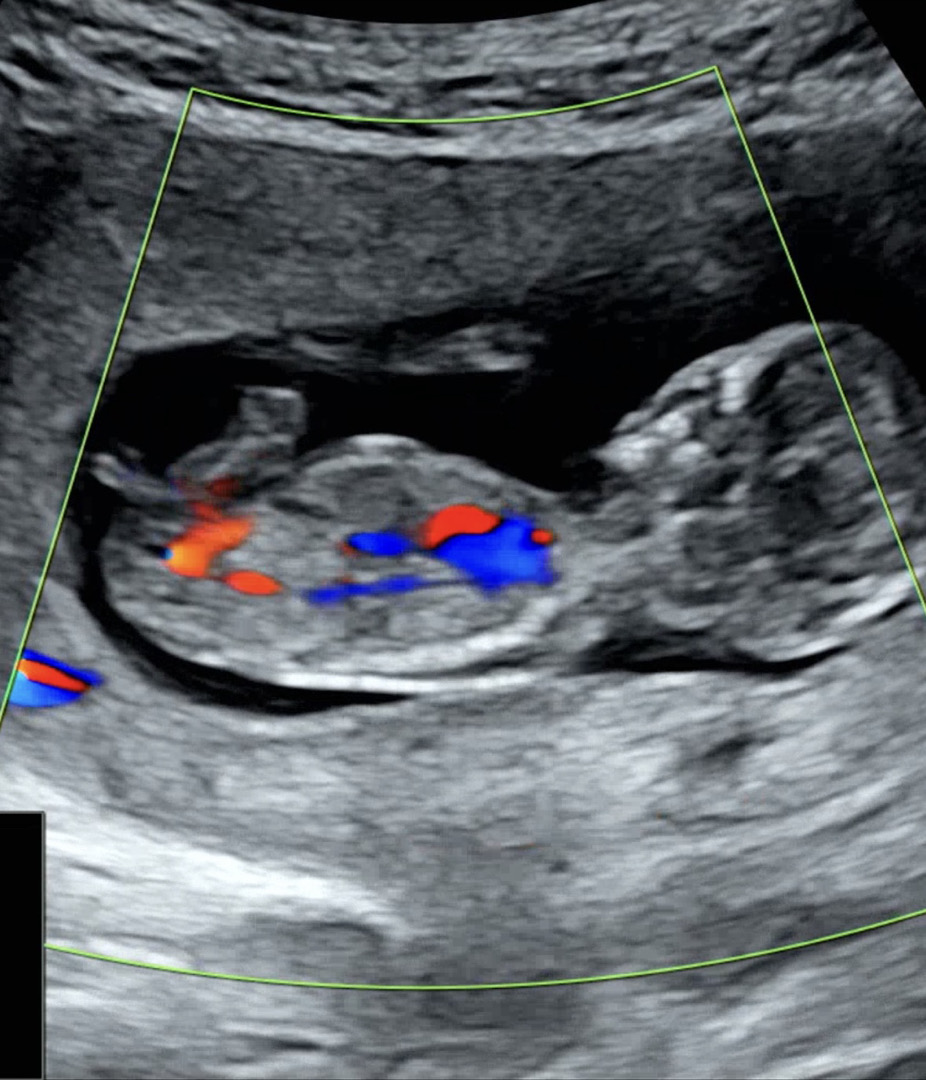

12주2일 각도법

갈라져 있긴한데 딸 아들 뭘까요?

각도상 올라간게 아들이네요

아들에 한표요!